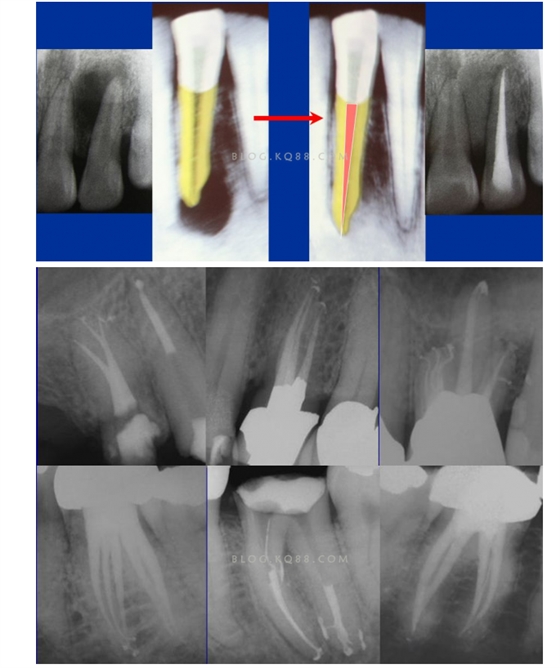

1簡(jiǎn)化難度 一個(gè)牙齒的根管治療難易程度不單單是根管的彎曲、細(xì)小、牙位、是否再治療決定的,開(kāi)髓的直線進(jìn)入和根管口的預(yù)先恰當(dāng)處理可以簡(jiǎn)化很大的難度,開(kāi)髓是根管成敗的基礎(chǔ)。對(duì)于彎曲根管冠部的直線入口就顯得尤為重要,冠部良好的直線入口可以避免側(cè)穿、臺(tái)階、遺漏根管等問(wèn)題的發(fā)生,冠部直線入口形成的良好情況,取決于醫(yī)生的理念和合理的器械選擇。開(kāi)髓孔的大小不是由醫(yī)生和患者的意愿決定的,而是由要治療牙齒的髓腔大小決定的。

5、預(yù)備到多少號(hào)結(jié)束根管預(yù)備理想的情況應(yīng)該預(yù)備到多大錐度,多少號(hào),預(yù)備后根管空間是金字塔還是埃菲爾鐵塔。專家經(jīng)過(guò)離體牙根尖切片研究發(fā)現(xiàn)根尖狹窄部遠(yuǎn)比想象的要大,如果根管預(yù)備太小就會(huì)殘留感染物,根管的部分空間就不會(huì)預(yù)備到,殘留的感染物就會(huì)造成治療效果達(dá)不到預(yù)期目標(biāo)。只有做到了充分的預(yù)備,盡可能的多沖洗才會(huì)有好的結(jié)果。

根管治療要做到看清楚,去干凈,充恰滿,封嚴(yán)密,就會(huì)達(dá)到期望的結(jié)果。2200年前的病例只充填了冠1/3可以理解、可以接受;2200年后的今天我們有先進(jìn)的設(shè)備和材料,就要充填出大錐度高密度的完美結(jié)果。理念決定技術(shù),標(biāo)準(zhǔn)決定技術(shù)的提高和進(jìn)步。